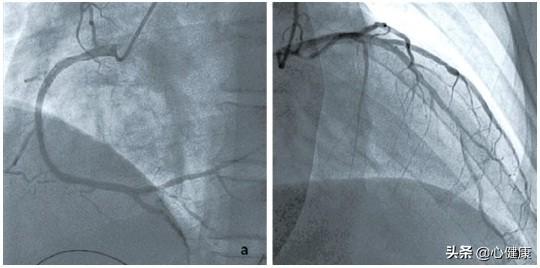

Comment se produit la sténose cardiovasculaire ?Le changement pathologique sous-jacent à la sténose cardiovasculaire est l'athérosclérose, d'où le nom complet de la maladie coronarienne : maladie coronarienne athéroscléreuse. De toute évidence, la sténose cardiovasculaire est causée par la formation de plaques d'athérome, dont la taille augmente progressivement, entraînant un rétrécissement graduel des vaisseaux sanguins jusqu'à ce qu'ils soient complètement obstrués. La rupture soudaine de la plaque, entraînant la formation de caillots sanguins, est un facteur de développement de l'infarctus du myocarde.

Toutefois, s'il est impossible d'inverser la formation de la plaque, il est possible de la ralentir grâce à des médicaments et à des interventions sur le mode de vie. C'est pourquoi de nombreuses personnes âgées peuvent vivre aussi longtemps et en bonne santé que les personnes normales, même si elles présentent une plaque. D'une manière générale, les médecins évaluent le risque élevé de maladie cardiovasculaire, ainsi que la sténose de l'artère coronaire de plus de 50 % des patients diagnostiqués avec une maladie coronarienne, il est nécessaire de commencer un traitement médicamenteux. Les médicaments couramment utilisés comprennent les statines stabilisatrices de plaque telles que le Ruijie, les médicaments antiagrégants plaquettaires tels que l'aspirine, etc. qui est le médicament de base, mais aussi les médicaments antihypertenseurs pour la maladie d'origine, les médicaments hypoglycémiques, etc. Les esters, tels que le mononitrate d'isosorbide Xincang, etc., sont également des médicaments de base. Pour les patients souffrant d'une sténose cardiovasculaire à 80 %, l'état a été prédit comme étant plus grave, et l'on pense généralement que lorsque la sténose est supérieure à 70 %, le patient devra subir la pose d'un stent pour débloquer les vaisseaux sanguins obstrués et aider à rétablir l'apport sanguin normal au myocarde, faute de quoi le patient peut être confronté à un infarctus à tout moment !的Risques. En d'autres termes, pour les patients présentant une sténose cardiovasculaire de 80 %, il peut être difficile de maintenir la vie du patient avec la médecine traditionnelle chinoise ou la médecine occidentale, sans parler d'une guérison complète, et seule la pose d'un stent ou d'un pontage peut sauver la vie du patient.

Une sténose cardiovasculaire de plus de 50 % est appelée maladie coronarienne, lorsqu'elle est supérieure à 70 %, une angine peut survenir, et lorsqu'elle est de 80 %, il s'agit déjà d'une sténose sévère. Qu'elle soit stable ou instable, l'angine peut survenir après un effort, une activité ou un exercice. Si elle est instable, l'angine peut survenir même au repos, et même une rupture de plaque peut se produire, formant un caillot sanguin et déclenchant un infarctus du myocarde.

Pour 80 % des sténoses, il est nécessaire de mener une vie saine, d'arrêter de fumer et de boire, de contrôler son poids, d'avoir une alimentation saine et de suivre un traitement médicamenteux régulier ; même une partie de la population a besoin d'une endoprothèse ou même d'un pontage pour résoudre cette sténose grave.

3. la disparition des symptômes ne signifie pas la guérison, mais seulement le contrôle ; sans oublier comment la sténose de 80 % a-t-elle été diagnostiquée ? S'agit-il d'un scanner coronaire ou d'une angiographie coronaire, s'agit-il d'un vaisseau majeur ou d'un petit vaisseau ? Le scanner ou l'angiographie ont-ils été revus après la guérison, et de combien la sténose de 80 % a-t-elle diminué après l'examen ?